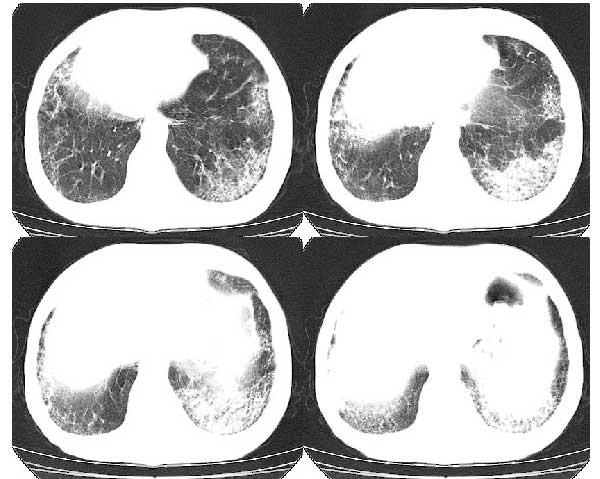

以下是引用扬仪在2005-5-12 20:46:40的发言:[br]右肺呈术后改变;双侧肺野散在分布斑片状、点状高密度病灶,(似可见“树芽征”);左上尖后段见斑团状高密度病灶(2个层面?),边缘毛糙,段性分布,与斜裂相邻,临近胸膜粘连;增强示病灶边缘强化,内呈水样密度;心影、纵隔右移,内可见4r淋巴结肿大。[br]意见:1、双肺继发性肺结核,左上为干酪病灶;[br] 2、矽肺合并感染;[br] 3、建议抗痨+抗炎。 [br]愚人之见,请高人指教!